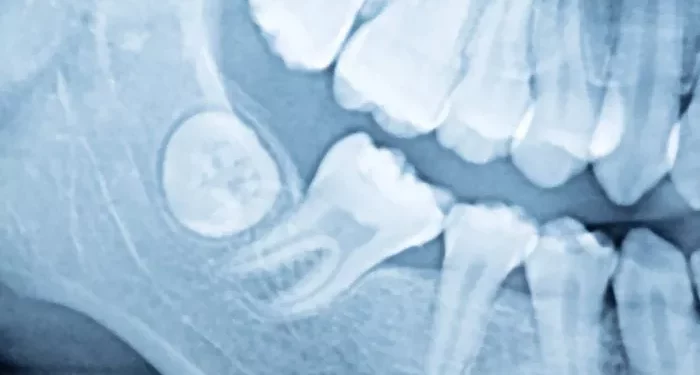

The research focused on patients undergoing the common but painful procedure of impacted wisdom tooth removal. In this randomized trial, half of the participants were given hydrocodone combined with acetaminophen, while the other half received acetaminophen and ibuprofen. Patients reported pain levels and other recovery indicators, such as sleep quality, during the week following the surgery.